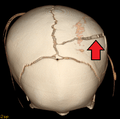

-

3D CT reconstruction showing a skull fracture in an infant